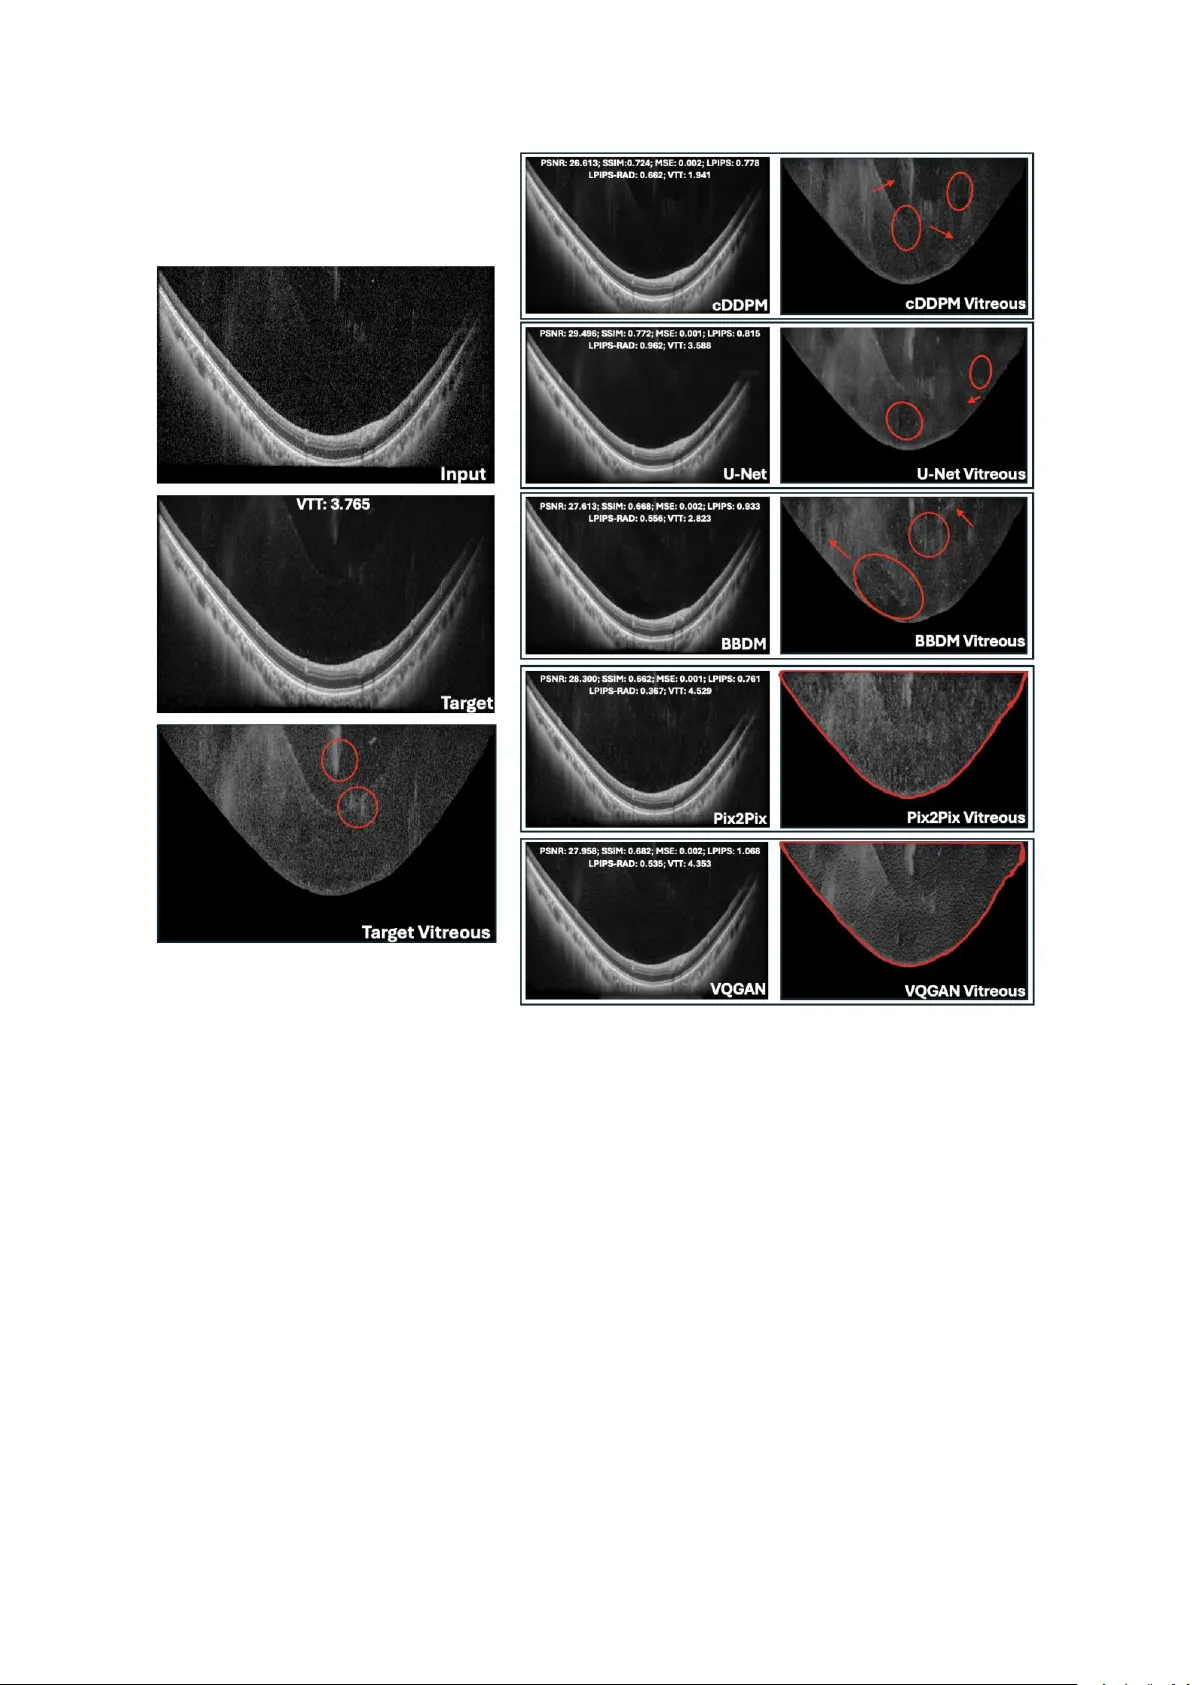

Deep Generative Models for Enhanced Vit reous OCT Imaging Simone Sar rocco 1 , Ph ilippe C. Cattin 1 , Peter M. Maloca 1,2 ,3 , Paul Friedrich *,1 , Philippe Valmaggia *,1,2,3 * Shared last authorship 1 Depa rtme nt of Biomedi c al Enginee r ing, University of Basel, Allschw il, Switzerla nd 2 Depa rtme nt of O phthal mology, University Hospital Basel, Basel, Switzerland 3 Moorfields Eye Hospital NHS Fou ndation Trust, London, EC1 V 2PD , United Kingdo m Corres pon ding author: Simon e Sarrocco, Department of Bio m edical Engineering, Unive rs ity of Basel, Allschwil, Switzerland . Email: simon e.sarrocco@unibas.ch Commercial relationshi ps: Simone Sarr occo: None Philippe C. Catt in: None Peter M. Maloca: Consultant at Roche, Zeiss Forum, and holds i ntellectual prope rty for machin e learning a t MIMO AG and Visio nAI, Switzerland. Paul Fried r ich: None Philippe Valmagg ia: Recipien t of Heidelberg Engineering and Ba y er, Funding from Swiss Na ti onal Science Foundation (Grant 323530_ 199395), Swiss Academy of Medical Science s (YTCR 43/23) and Jangg en -Pöhn Foundation. Keywords: optical coherence tomograph y, vitreous bo dy , imag e qu ality enhanceme nt, dee p learning , diffusion models, visual Turing test , U -Net, Pix2Pix, VQ- GAN Abstrac t Purpose : To evalua te de ep lea r ning (DL) m odel s for enhancing vi treous optical coherence tomography (OCT) image quality and reducing acquisition t ime. Methods : Condi tional Denoising Diffusion Pro babilistic Models (cDD PM s), Bro wnian Bridge Di ffusi on Models (BBD Ms), U-Net, Pi x2Pix, a nd Ve ctor-Quan tised Gen erative Adversarial Network (VQ-GAN) were u s ed to generate high-q uality spectral-domain (SD) vitreous OCT images. Inp uts w ere SD AR T10 images, a nd o utputs were compared to pse udoAR T100 images o btained by a veraging ten ART10 image s p er eye location. Model perform ance was assessed using i mage quality me trics an d Visual Turing Tests, w here ophthalmologists ra nked ge nerated images a nd evaluated anatomi c al fid elity. The be st model’s performance wa s further tested within the manually seg mented vitreo us on newly acquired data. Results : U-Net achieved t he highest Peak Signal- to -Noise Ratio (PSNR: 30 .230) an d Structural Si milarity Index Measure (SSIM: 0 .820), foll owed by cDDPM . For Learned Perceptual Image Patch Simil arity (LPIPS), Pix2Pix (0.697) an d cDDPM (0.75 3) performed best. In the first Visua l Turing Test, cDDPM ranked highest (3.07); in the second (best model only) , cDDPM a chieved a 32.9% fool r ate and 85.7% a natomical preserva ti on. On newly acquire d data, cD DPM g enerated vitre ous regions m ore simila r in PSN R to the ART10 0 reference than true AR T1 or ART10 B -sca ns and achie v ed higher PSNR o n whole images when conditioned on ART1 than ART10. Conclusio ns : Resu lts reve al discrepancies between quan titativ e me trics and clinical evaluation , hig hlighting the n eed for combined assessment. cD DPM showed strong potential f or gene rating clinically meaningful vitreous OCT images while reducing acqui s ition time fourfold. Tra nslation al Relev ance : cDDPMs show pr omise for cl inical integration, supp orting faster, h ighe r-quality vitreous imaging. Dataset an d code will be ma de publicly available. Introd uction Optical coherence tomography (O CT) is a non -invasive im aging technique widely used in op hthalmology to visuali s e different compartments of the eye at micro met re -scale resolu ti on. 1 Despi te its widespread adop tion , O CT imagin g faces chal lenges, particularly in acquiring high-q uality images of the vitreous body , wh ose main function is to remain transparent. 2 Due t o its transparency, it is not easy to pr operly visualise it through im aging techniques. 3 Recent work by Spa ide et al. ha s introduce d an enhanced imaging technique aimed at i mproving the visuali sation of the vitreous body , allowing for a n eva luation of a natomic chan ges in the vi treous associated wi th posterio r vitreous d etachment, vitreo us degeneration and cisterns. 3,4 This approach invol v es a veraging fou r A -scans a t each position before image reconstruction, signi fic antly boo sti ng image quality through detai led frame averaging a nd high - resolu ti on imaging . Howe v er, obtain ing high -quality OCT scans ca n take seve ral minutes, sign ificant ly burden ing patients an d reducing cli nical efficie ncy. Another limi tation i s the presen c e of sp eckle , a g ranula r p attern i nherent to O CT ima ging that often obscu res fin e structural details. 5 Speckles a rise from the interference o f coherent light waves scattered by micro structures within tissue, leading to random inten s ity and phase variations. In OCT, thi s mani fests as a gran ular, grainy texture that red uces i mage contrast a nd obscure s fine an atomical d etails , thereby decreasing o verall imag e quality and diagnost ic clarity. 5,6 In addition, OCT image s are a lso aff ected by artef acts due to p atient motion during the acquisition , which results in long st rips of bl ack pixels that might comple tely obscure p arts of the images. There h ave b een many d ifferent ap proaches to enhan ce the quality of OCT ima ges. A common denoising technique is signal a veraging . 7 It consists of sequentially acqui r ing multiple scans o f the same eye locati on and a veraging th em in magnitude to increa se the o verall quality of the i m age . 8 Also, cl assical denoi s ing approache s, such as med ian filtering , sparse and wavelet-based filtering metho ds, and Bay esian techniques , h ave sh own some promi se i n re ducing n oise in OCT imag es . 9– 11 Re cent breakthrough s in mach ine le arning h ave given rise to deep neural ne tworks . Mode ls like con volutional neural ne tw orks (C NNs ) and g enerative a dversarial netwo rks (GANs ) have been e m ployed on medical i m ages for many different tasks , i ncluding OCT image enhancement. 12 – 14 Howe v er, ea ch of the me ntioned method s has its li mitations. Trad itional de noising approache s , such a s filtering metho ds and Bayesian techniques, often bl ur critical anatomi c al details or requ ire extensive parameter tuning , thereby limiting their clinical utility. 15 Whe n performing signal ave raging, the o verall acquisition time increases linearly in  , crea ting a burden for the patient and introducing motion a rtefacts. 16 In multi-frame averaging, motion causes local misalignment b etween B -scans, especially at the e dges where fewer frames overlap. This prod uces da rk bands o r b lack strips that p artially o r co mpletely obscure affected region s . CNNs a nd GANs were able to gene r ate better results thanks t o the deep arc hit ecture of deep le arning mod els . 14,17,18 Howe v er, they are s till prone to un stable trai ning , introdu ction of artefacts a nd blurriness in the outp ut images . 19 More re cently, d iffusion models, a n ew class o f dee p g enerative models, have be en emplo y ed for many image- to -image translation tasks. 20 – 23 Thanks to thei r ability to preserve fin e image detail s, they have be en wid ely used in the med ical fiel d to enhance the q uality of the image s. 24,25 Therefore, i n this wo rk, we p ropose app lying diffusion models for enhancing vitreous OCT images a nd compare their performance with other well-known de ep le arning models , like U-Net, Pix2Pix, an d VQ-GAN. 26 – 28 The pe rformance of ea ch model is assessed from both a quantitative and qualitative perspe ctiv e. For the qu antitative comparison, stan dard image quali ty metrics like PSNR, MSE, SSIM , an d L PIPS are use d to measu re the similarity b etween the gene r ated i mages and the original high-qual ity OCT imag e; for the qu alitative assessmen t, the model o utputs a r e compared by visual insp ection , bo th g lobally across the entire image a nd specifically w ithin t he vitreo us region by masking out all other structures. The clin ic al va lue is assesse d via two visual Turing tests performed by expert ophthalmologists from t he University H ospital Bas el and ot her clin ical sites. 29,30 Add itiona lly, a qu antitative eva lua ti on wi thin the regions of interest i nside the vitreous body is p erformed on newly acquired data comprise d of AR T1, ART10, an d ART100 volumes that sh ow t he f ull gr adation f or a proper comparison . In this way, we aim to i dentify a d eep learning -based approac h capable of en hancing the qu ali ty of vitreous OCT images by si gnificantly reducing acquisition times with respect to acqui r ing an ART1 00 i mage and potentially bein g deployed in clinic al practice . The code, tog ether with the d ataset and the vi sual Turing tests, w ill be made publicly available at https:// github .com/SimoneSarro cc o/vitreous_enh ancement . Methods Data Ac qui sition The ma in dataset used in this study consisted of retin al s pectral - domain (SD ) OCT image s from six he althy sub jects at the University Hospital Basel using a Spectrali s OCT devi ce (H eidelberg En gineering GmbH , Heidelberg, Germany ) i n AR T10 mod e . Follow - up da ta, used to e valua te the p erformance of the best model insid e the vitreous body, con sisted of retinal SD OCT image s acquired in Lucerne from one healthy subje ct usi ng the sa me device as the ma in dataset, in ART1, ART10, a nd ART100 mode s . Ethical approval for data collection was granted from the Eth ics Committee of Northwe st and Central Switzerland (ID: EKNZ 2022 -01091), and all participants provided i nformed written consent. The an onymised d ata we re transferred under a coded data-sharing a greement to the De partment of Biomedi cal Engineering o f the Unive rs ity of Basel. The OCT i mages of b oth datase ts w ere acquired in v ideo mode, ge nerating consecu tiv e B-scans of 768  496 pi x els on a 55 ° field- of -view . The n ominal acqui s ition sp eed w as set at 20 kHz, co rresponding t o an inte gration time of 44  per scan. F or the main dataset, for each scan location , ten ART10 images were acqui red , where each ART10 is in turn the average of ten consecu tiv e B-scans. Since a total of 132 different lo cations were scanned, the datase t consisted of 132 0 ART10 imag es, from he re on wards also denoted as l ow -quality images or input images. For the follo w- up da taset, ten ART1 volume s, ten ART10 volumes, and o ne ART100 volume were acqui r ed on the same pa ti ent, w here e ach volume consi ste d of 21 B -sc ans (i.e., 21 different eye loca ti ons). Weighted Sign al Averaging Figure 1 . Schematic representation of the ste ps for gen erating the gr ound truth and vi sual comparison with a simp le signal av eraging without artefact detectio n . a) T he steps performed to detect and mask out the arte fact regions in each ART10 image are shown: 1) A binary mask of the origina l ART10 image is computed with a th reshold of 0 to ke ep only b lack pixels. 2) T he m orphological closing operation is ap plied to fill small ga ps between ne ar by black pixe ls w ith white pixels, th us keeping only conti guous re gions of black pixels. 3) R efinement checks are a pplied to ke ep only those black pixels tha t are surrounded by other black pixels in at least 3 of the 4 differen t directions (up, down, left, right) so that small protuberances are removed from the mask. 4) The contours of the black region are drawn on t he o riginal ART10 i mage, showing a perfect match with the mo tion artefact r egion (long, contiguo us region of only black pixels at the botto m of the image ). b) Visual comparison betwe en the prop osed w eighted signal averaging (left i mage) and simple arit hmetic si gnal av eraging (righ t image) for generating t he ground truth. As shown in the zoom ed area in th e red rec tang l e , the proposed appr oach led to an in creased level of de tail and b rightness in re gions where many input ART10 images had a motion artefact. In Fig ure 1a, a visualisatio n of the main steps of the p roposed averaging method i s provided. Since many input images had mo tion art efacts , we developed a w eighte d image averaging me thod to g enerate the grou nd truth . Motion artefacts appe ar as long black strips that co mpletely o bscure part o f the image. To detect the m in ea c h o f the ART10 image s, a comb ination of binary threshold ing and morphological operations was used to i solate contiguous strips of black pixels . Then, the fina l a veraged i mage (i.e., the ground truth) was generated by assigni ng a w eight of 0 to all p ixels i nside the detected artefact re gion s a nd a w eight of 1 otherw ise. 31 In other words, each pi xel in the grou nd truth i mage is the average of all non -artefact corresponding pixels in the input images . As sh own in Figure 1b , t his ma sk ed averaging a pproach result ed in an enhanced ground t ruth imag e with less shadowi ng eff ect and a better level of con trast in the regions w ith many motion artefacts in the ART10 images . Since a target image at each eye l ocation was g enera te d by a veraging the ten ART10 of the same loca tion, w here each o f them was in turn the a verage of ten consecutive B-scans, we re ferred to it a s p seud oART100 , repre senting the average o f 1 00 B - scans, yet not acquired w ith the original ART100 sett ings. Preprocessing For each pa ir, inpu t a nd target images w ere normali s ed to a p ixel i ntensity ra nge of [0,1] by min-max no rmalisation . Padding of 8 rows of bla ck pixels, both at the top and at the b ottom of each image , wa s app lied to make the ima ges co mpatible w ith the architecture of the models . The fin al pre-pro cessed images, ready to be fed in to th e model s, were graysca le vitreous OCT images of size 768  512 pixels. Model Architecture s Many d ifferent de ep learning models we r e i nclu ded in the comparison , including two different kinds of diffusio n models: cDDPMs and BBDMs. 20,32 – 34 Diffusion models aim to en hance the quality of the ART10 image s by a dding d ifferent levels of noise to th e correspondi ng p seudoART100 and learning to i teratively denoise them. 20 After learning th e de noising process on the p seudoART100, only the ART10 i mage is given as in put to the model, which returns its enhanced versi on by iteratively re movin g the noise pattern learn ed during training . 35 The two models were compared with a U -Net, and adversa r ial networks like Pix2Pix and VQ-GAN. 27,28,3 6 A more extensive explanatio n of eac h model architecture is provided in Supplementary Material 1. Tra ini ng Details Table 1. Best config uration parameters for e ach deep learning model Parameter U-Net cDDPM BBDM Pix2 Pi x VQGAN Image Size 768x512 768x512 768x512 768x512 768x512 Batch Size 1 1 1 1 1 Learning Rate 2e -5 2e -5 2e -5 2e - 4 G: 1e-4, D: 5 e-4 Optimi zer AdamW AdamW Adam AdamW Adam Weight Decay 0.01 0.01 0.01 Linearly decaying the learning rate to 0 from epoch 100 0.01 Dropout 0.1 0.1 0.0 0.0 0.1 Best Epoch 50 300 170 200 10 Numb er of Channels 128 128 128 G: 128, D : 64 G: 512, D :64 Training Timesteps - 1000 1000 - - Sampling Timesteps - 1000 200 - - Variance schedule - Linear Linear - - Channel Multiplier (0.5, 1, 1, 2, 2, 4, 4) (0.5, 1, 1, 2, 2, 4, 4) (1, 2, 4, 6, 8) (1, 2, 4, 8) (1, 2) Attent ion Resol utions 16, 8 16, 8 128, 64, 32, 16, 8 - - Numb er of Attent ion Heads 1 1 8 - - Numb er of Heads per Channel 1 1 64 - - Numb er of Residual Blocks 2 2 2 - 2 Emb edding Dimension - - 8 - 8 Numb er of Emb edding Vectors - - 16,384 - 16,384 Loss Type L2 L2 L1 10  L1 + LSGAN L1 + 0.01  Adv + 0.001  Perc Discriminator - - - PatchGAN PatchGAN EMA 0.9999 0.9999 0.995 - - DDPM = Deno ising Diffusion Probabilistic Model; BBDM = Brownian -Bridge Diffusion Model; VQGAN = Vector-Quan tized Generative Adversarial Network; G = Generator; D = Discriminator; L1 = Mean Absolute Err or; L2 = Mean Squared Error; LSGAN = Leas t-squared GAN; Adv = Adversarial Loss; Perc = Per ceptual Loss. To train a nd eva luate the mo dels , the datase t was spl it into train ing (9 90 pa irs of image s), validation (160 pai rs), and test sets (170 p airs) i n a patien t -wise man ner to avoid having OCT scans of the same patie nt in more than one set . The train ing se t comprised image s from 4 p atients, whe reas th e valid ation and test sets comp rised image s from 1 patient each. The validation set was used to choose the best setup for each model; the test set was used to compare the best-p erforming configurations and assess the best model from a quantitative perspective. F or the BBDM, instead of using the pre-trai ned che ckpoi nts o f the VQ -GAN p rovided by the authors , which were trained on R GB images from the Ce lebAMask-HQ dataset, we trained our own la te nt space on b oth ART10 and pseud oART100 images from our traini ng se t to make i t more suitable for reconstructin g gra ysc ale vitreou s OCT imag es. 37 The hyperparame ter ch oices o f each best-performing se tup are shown in Tab le 1 . All model s were trained and tested on a single N VIDIA® Quadro R TX 60 00 24 GB (Nvidia, Santa Clara , US). Evaluation Metrics Quantitative eva luation was performed usi ng both pixel -wise metrics like PSNR and MSE , and similari ty and pe rceptua l me asures like SSIM and LPIPS, resp ectively. 38,39 All metrics w ere comp uted be tween o utput images and the co rresponding ground truth. Moreo ver, sin ce the ori ginal LPIPS is b as ed on a C NN a rchitecture pre -trained on Imag eNet (i.e., RGB no n-me dical images), we decid ed to also use a versi on of LPIPS pre-trai ned on the RadImageNe t dataset, which we called LPIPS-R AD. The latter can be found i nside the MONAI Generative repository . 40,41 To e valua te cl inical applicability, re levance, a nd usa bility, expe rt o phthalmologists condu cted two visual Turing tests and rated the models. The g raders for the visual Turing tests were recruited throu gh a req uest via professional ophthalmology n etworks of the Moorfie lds Eye Ho spital, London, U K, and the U niversi ty Eye Hospi tal, Unive rs ity of Base l, Switzerla nd. The first test consi sted of ten qu estions , whe re i n each of them a true low-q uality OCT i mage (i.e., AR T10) was shown together w ith the Figure 2. Str ucture of the two v isual T uring te sts . In P anel a (above), the re is an examp l e of a question from the fi rst visual Turing test, wh ere clinicians were asked to rank the 6 model outputs displayed at the bottom of the page from best (left) to wor st (right). B y clicki ng on one of the 6 images below, they could visualise it in full resolution side- by -sid e with the low -qua lity imag e (ART10, always displayed on the top left). In Panel b (bottom-lef t), a question fro m the first section of the second visu al Tur ing test is shown, where clinicians had to s po t the ps eudoART100. In this p art, t hey coul d zoom i n on specific p arts of both images using a synchronised mag nifier that appeared on both images. In Panel c (bottom-r ight), a represen t ation of the second section of the secon d visual Turing t est is sh own. Here, ophth almologists ha d to compare the ps eudo ART100 with the generated image using a slide r, to the n answer a ll the sub -que stions related to the preservation o f ana tomical details both in the vitreous body and in o ther compartments of the eye. correspondi ng five model o utputs plus the “true” h igh -quality image ( i.e., the pseudoART10 0 used as ground truth i n o ur study). In e ach q uestion, ophthalmologists were asked to ra nk the six im ages from best (rank 1 ) to worst (rank 6) based on wh ich they thou ght w as the best artificial ly generated enha nced versio n of the ART10 . In Figure 2a , the structure o f the first visual Turing test is displayed , and i t can be accessed at htt ps://v0-visualturingtest-rho.vercel.app/ . The second visu al Turing test was performed using the o utput i mages from the de ep learning model that performed best i n the first test. The test w as di vided into two sections , each of ten questions . I n the first section (Figure 2b ), in each question, they had to spot the “real” hi gh -quality OCT imag e, and the fool rate was compu ted as the percen ta ge of wrong answers . 42 In the second se ction (Figure 2c), in each que sti on, they had to answer a set o f Yes/No sub-questions regarding the preservation of anatomi c al details o f both the vitreo us b ody and other rele vant anatomical structures of the eye (Su pplementary Ma terial 2). This se cond test can be a ccessed at h ttps:/ /v0- new -project-atjqtgf4o4e.vercel.app/ . Bo th Turi ng tests w ere created a nd deployed using the cloud pl atform Vercel (Vercel, San Francisco, US). Since each e ye location i ncluded ten similar ART10 i mages, we randomly chose one per locatio n to preven t multiple image s from the sa me location from app earing in the two visual tests. How ever, since the s econd test consisted of a t otal of twenty questions (i.e., twen ty d ifferent images), for three of the ey e loc ations o f the patient included i n our test se t, we had to p ick two images. Once the image s to be included in the visual test we re randoml y sel ected, we al ways showed the same set of image pairs in each question to all participants. Results Quali tative Comparison Figure 3 . Visual comparison of model outputs and tar get image with an additional focus on the vitreous body. In the le ftmost column, in put A RT10, target pseudoART100, an d t he segmented vitreou s of the target f or an example from t he t est set are displayed. In the two colum ns on the righ t, the model outputs from ea ch o f the five DL models and the cor responding vit reous extracted by masking out all o ther ana t omical features in the image are shown, respect ively. B efor e segmenting the vitreous body, histogram equalisation was applied using the open -sour ce Fiji ima ging s oftware to enhance t he contra st f or a better visu alisation. 44 The se gmentations w ere obtained by using th e S egm ent Anything demo , and they might slightly diff er at the edges. 51,52 In red, some a rtefacts for each image are highlighte d with ci rcles and arrows. For Pix2Pix and VQG AN, the whole r egion is hi ghlighted beca use of the p resen c e of to o m any artefacts. Additionally, at the top of each generated image, th e sco res of all quan titative metrics with respect to the ground truth and the average rank score from the first visual Tur ing test ar e displayed. P SNR = Peak Signal- to -Nois e Ratio; S SIM = S tructural S imilarity In dex Measu re; MSE = Me an S quared Error; LPIPS = Learne d Perceptual Ima ge Patc h Similarity; LPIP S - RAD = LPIPS pre-tra ined o n RadImage Net; V TT = average ran ki ng from the first Visual Turing Test. Figure 3 displays an exa mple o riginal AR T10 imag e with a motion artefact a t the bottom tha t obscures the choroid and the sclera. In this region, the reconstructions in the mo del outputs are very different from e ach o ther. For i nstance, i n the output ima ge from the U-Net model, no meaningful anatomical details were recon structed, but rather a b lurry re gion mostly filled with pi x els of average i ntensity . A simi lar behavio ur can be seen in the ou tp uts from the two GANs, where the re is a sort of grid-shaped artefact in the output f rom Pix2Pix a nd a strip-shaped ar tefact in VQ-GAN. On the other hand, the two di ffusion mod els we re able to reco nst ruct the anatomi c al structures of the choroid in a way that resembles the gro und truth. When looking a t the retin al l ayers, in the output from the BBDM, the bo undaries between each laye r are less de fined than in the targe t image. In the case o f VQ-GAN a nd U -Net, the layers a re cl early visible , but there is a gen eral loss of detail withi n each layer, w here the reconstructio n appear s to be ve ry ho mogen eous a nd o verly smoothe d . When iso lating the vitreou s reg ion of the images by masking out all other an atomi cal structures , artefacts were vi sible across all model s. The U-Ne t output showed a g eneral lo ss o f fine details du e to blurriness , along w ith se veral localised a rtefacts (hig hlighted by re d ci rcles a nd arr ows in Fig ure 3). Both diffusion -based models also pro duced artefacts w ithin the vitreous region, with the BBDM generating anatomical st ructures that differed completely from the target. The vitreous gen erated by the cDDPM and the U -Net appe ared simil ar, with the U-N et o utput being smoother a nd da rk er, whi le the cDDPM sho wed a texture pattern mo re consi ste nt with the targe t but containing a few di storted structures. In add ition, both GANs exhibited the same repeating texture patterns across the whole Figure 4. Add itional visual comparison o f the mo del outpu ts with the tar get ima ge. On the l eft, the ART10 image used a s i nput i n ea ch of th e mod els is s hown. O n the two c olumns on t he right, th e output image from each of the five de ep learning models, together with the ta rget pseudo ART100 ima ge us ed as ground truth. Also, on top of each im age, the sco res of all quantitative metr ics and the average r anking from the first visual Tu ring te st are d is played. PSNR = Peak Signa l- to - Noise Ratio; SS IM = Structural Similarity In dex Measure; M SE = Mean S quared Error; LPIPS = Learned Perceptu al Im age Patch Similarity; LPIPS -RAD = LPIPS pre-trained o n RadImageNet; V TT = av erage ranking from the first Visual Turing Test. vitreous as i n the co rrespondin g g lobal i mage s. It is wo rth n oting tha t the ori ginal acqui s itions we re al so not free of artefacts. For in stance, in this case, the target i mage presen ts mostly mirroring artefacts, which genera te d stal actite-like hyperintense regions . In Figure 4, there is an example of an input ART1 0 with a signific ant amount of spe ckle . It is ea sy to n otice that in the case of Pix2Pix, t he speckl es are n ot sufficien tly reduced, and the ov erall quality of the input ART10 image is not enhanced . Al so in this case, and many cases amon g the test set, the output from the VQ-GAN presented a w ave effect across the whole ima ge. The retinal la yers in the outpu t images from the U -Ne t and BBDM we re di storte d wi th no clear boun daries . In co ntrast, in the reco nstructed image from the cDDPM, they are well reconstructed an d d elineated as in the gro und truth. The only exception is the retinal pigment epithelium , which is const antly brighter than the ground truth . Quanti tative Comparison Table 2. Quantit ative Metrics on the Test Set (mean ± standard devi ation) Metrics U-Net cDDPM BBDM Pix2 Pi x VQ -GAN Input/Target PSNR 30.230 ± 2.089 28.6 15 ± 1.769 27.5 70 ± 1.326 28.46 8 ± 1.697 28.962 ± 1.769 25.336 ± 2.067 SSIM 0.820 ± 0.041 0.771 ± 0.043 0.711 ± 0.041 0.719 ± 0.041 0.748 ± 0.048 0.518 ± 0.072 MSE 0.001 ± 0.001 0.002 ± 0.001 0.002 ± 0.001 0.002 ± 0.001 0.001 ± 0.001 0.003 ± 0.002 LPIP S 0.838 ± 0.062 0.753 ± 0.067 0.870 ± 0.061 0. 697 ± 0.0 58 0.986 ± 0.052 0.823 ± 0.081 LPIP S-RAD 1.069 ± 0.073 0.627 ± 0.107 0.445 ± 0.091 0.267 ± 0.092 0.552 ± 0.054 0.894 ± 0.098 Avg. sampling time (s) <1 96 7 <1 <1 - GPU Training usage 17342 MiB 9196 MiB 6318 MiB 4700 MiB 13638 MiB - The a rrows indicate if higher (pointing up) o r lower (pointing down) values cor respond to better re sults. PSNR = Pea k S ignal- to -No ise Ratio; S SIM = S tructu ral Similarity Index Measure; MSE = Me an Squared Error; LPIPS = Learned Pe rceptual I mage Patch Similarity; LPIPS-RAD = LPIPS pre-trained on RadIma geNet. In bold, the best scores for each metric. The quantitative results a re presented i n Tabl e 2. In the last co lumn, the metrics between inpu t ART10 a nd target pseudoART100 are computed to have baseline Figure 5. Differe nce ma ps b etween ge nerated im ages a nd g round tr uth. In the first column, the grou nd truths o f three sa mples from the test set are sho wn. Each of the five followin g colu mns sh ows the generated image (le ft) and the corresponding diffe renc e map (right) for on e of the five dee p learning mode ls. The d ifferences are computed a s the generated i mage minu s grou nd truth, where both images are in the range [0,1], leading to differences in th e range [-1,1]. Red col ours: p ositive differences; blue colours: nega tive differences. value s for better u nderstanding the p erformanc e o f each model in ge nerating images more simil ar to the ground truth tha n the ART10. The U-N et model ach ieved the best results on all pixe l -based metrics, w ith a PSNR o f 30.230 ± 2.089 and an MSE of 0 .001 ± 0.00 1 . VQGAN, cDDPM, a nd Pix2Pix achie v ed similar values of PSNR (VQGAN: 28.962 ± 1. 769 ; cDDPM: 28.61 5 ± 1.769; Pix2Pix: 28.468 ± 1.697). In Figure 5, pixel - wise differences b etween model output and g r ound truth of three randomly ch osen image s from the test set a re displayed. For each model, b oth the gene r ated i m age and the dif ference map are shown, where red colo urs represent p ositive d ifferences (i.e., pixel value of the genera ted image larger than the grou nd truth), bl ue co lours represent negative differences (i.e. pixel value of t he gen erated imag e lo wer t han the ground truth), and white means no difference. Most of t he model s s eemed to st rugg le with the reconstruction of the same anatomical struct ures, li ke t h e nerve fibre layer and other retinal layers in the first sample (f irst ro w of Figure 5 ), or the right part of the image in the second sample (s econd row of Figure 5). Pix2 P ix, most of the time, co uld not reconstruct the v itreous body, as can be e asily spotted from the d ifference map of the first sample , w here the predicted pixel i nt ensitie s were always higher tha n the ground truth. In terms of SSI M, U-Net also performed be st ( 0.820 ± 0.041). The cDDPM was the second b est, with an average of 0.771 ± 0.043 , f ollo wed by VQ -GAN (0.748 ± 0.048 ), Pix2Pix (0.719 ± 0 .041), a nd BBDM (0 .711 ± 0.041). When l ooking a t the pe rc eptual metrics , Pi x2Pix performed best in terms of b oth LPIPS (0.697 ± 0.058 ) and LPIPS- RAD (0.267 ± 0.092). U - Net , on the other hand, generated i mages that were e ven l ess simila r to t he groun d truth than the input ART10 accord ing t o both LPIPS (U-Net: 0.838 ± 0.062; Baseli ne: 0.823 ± 0.081) an d LPIPS-RAD (U -Net: 1.069 ± 0.07 3; Base line : 0.894 ± 0.098). The same happe ned with the scores o f LPIPS for BBD M and VQ-GAN, both worse than the baseline v alu es shown i n the last column (BBDM: 0.870 ± 0.061; VQ -GAN: 0 .98 6 ± 0.052). Among the diffusio n mode ls, cDDPM performed bett er t han the BBDM in terms o f LPIPS (0.753 ± 0.067, BBDM: 0.870 ± 0.061), but worse in terms of LPIPS-RAD (0.627 ± 0.107, BBDM: 0.445 ± 0.091) . Visual Turing Tests Of the total o f 39 9 ophthalmologists con tacted, 17 participants (4.3% ) r egistered for the first Turi ng test, a nd 7 pa rticipants (1.8%) for the secon d Turing test. Among the 17 partici pants in the first vi sual t est, 13 had at least 5 years of e xperie nce with OCT i mages. In thi s test, the l ower the average rank, and closer to 1, the better the evaluation o f a model . The results are pre sented in Fig ure 6. The signal ave raging approach still perform ed better tha n all d eep lea rning models, with an average rank of 2.78. This means that, on avera ge, clin icians stil l preferred the “true” hi gh -quality Figure 6. Results from the first visual Turing te st. The average r anking s are sh own tog ethe r wit h the 95% confidence intervals. The low er the av erage rank for a mod el, and the closer to 1, the bett er the per formance. Models that are significantly worse tha n signal averaging (ad justed p -val ue < 0. 05, Holm-correcte d for multiple comparisons) are marked wit h a r ed dagger ( † ). image to the gene rated o nes. Amon g the deep lea r ning mod els, the cDDPM performed b est with an aver age rank of 3 .07, wit h the U -Net model right b elow it (3 .11). Pix2Pix and BBDM we re the worst, with a n average rank above 4 o ut of 6. When performing hypothesi s testing be tw een the results of the first visual test, as shown in Figure 6, only cD DPM and U-N et were no t significantly differen t from signal ave r aging, with adjusted p -values > 0.05 (Holm-co rr ected for multip le comparisons). 43 Whe n stratifying the ranki ngs by years of experience, a s sh own in Figure 7, the major difference was in the average ranking of the two GANs. In both sub -g roups, cD DPM and U-Net were still the closest to sig nal a v eraging, with al most the same ave rage score among clini cians w ith at least 5 years of e xperience. Since the cDDPM pe rform ed best among the deep learning model s in the first test, the image s generated w ith this mod el were use d for the seco nd test to h ave a more detailed cli nical eval uation . Among the 7 particip ants in the second visual test, si x had at least 5 yea rs of experie nce with OCT imag es. The results from both sectio ns are shown i n Figure 8 . In Section 1, the fool r ate, def ined as the percentage of how many times op hthalmologists wrongly stated that the genera ted image was the real high - quality OCT ima ge , was computed . The ideal fo ol ra te is 50%, which means that , on average, cli nicians ca nnot di stinguish be tween g enera ted and re al images . In our case, a mong the 7 participants, the average fool rate was 3 2.9%. In Se ction 2 , we computed the percentage of positive answers to questions rel ated to the preservation of t he most relevant anatomical features i n the images. The overall anatomical preserva ti on of all participant s was 85.7% . Whe n focusi ng on the vitreous body (Figure 8a), the an atomical pre servation was 78 .9%, with the low est percen tage occurring in the are a of Marteg iani (7 0% of pre servation), and the posterior vitreou s membrane being the most preserved structure (8 4.3 %) . From t he commen ts clinicians left when Figure 7 . Average ranks stratified by l evel of experience wit h OCT data . In blue, the average ranks among clinicians with less than 5 years of expe rience are sh own, whereas in orange, the corre sponding scores among clinicians with at least 5 years of experience are displayed, together with the 95% confidence intervals. To hel p understand how each mo del is ranked a mong t he two sub - grou ps, the ranking position is displayed at the bottom of each b ar. answe r ing “No”, we kn ow that in just one case, the hyalo cytes were visible in the ground truth but no t in the generated image. R egarding the o th er an atomica l compartmen ts of the eye (Figure 8b), the re tinal la yers w ere perfectly p reserve d with a percen tage of 100% , f ollo wed by the choroid (97 .1 %) . The lowe st preservation was about the i dentification o f pa th ological structures, whe re the percentage was 80 %. Here , we had the most heterogeneous answers, with ca ses in w hich the y spotted pathologi cal structures in 9 out of 10 images, especially dense vitreous, and c ases in which they spotted n one i n 9 out of 10. Figure 8 . P ercenta ge of a natomical p reservation for the vit reous body a nd oth er relevant anatom ic al structures. In Panel a (above), the percentages of positive answers for the vitreous body are sh own, which include the posterior vi treous m embrane, the bursa praemacularis, the area of Marte giani, and hyalocytes. I n Panel b (below), t he per c enta ge of positive answers for t he remaining key anatomical str uctures, like retinal laye rs, optic nerve head , choroid, scl era, a nd pathological structu res, is displayed. Quanti tative Evaluation of the Be st Model Inside the Vitreous Body The qu antitative performance of the cDDPM within subregions of the vitreous body was evaluated on the newly acquired data. Each ART volum e comprised 2 1 B-scans, Figure 9 . Qual itative a nd quan tit ative comparison o f tru e ART1 , ART10, a nd ART100 B - scans, and the co rresponding images generated by the cDD PM. In the first row, the true ART1, ART10, a nd ART1 00 B-scans at the sam e eye location ar e displayed. On the ART100 image, the ROI inside the vitreous body is highlighted in green. In the second row, fro m left to right, the images generated from the cDDPM by using e it her the ART1 B-s can or the ART10 B -scan a s conditioning are shown, respectively. In the last row, the correspond ing di fference m aps, c ompu ted on a pixel level as the generated image minus t he A RT100 ima ge, are dis played. Difference maps a re in the range [ -1, 1] since the y are computed between images in the pixel range [0,1]. thus 21 different eye locations. For each eye location , a region of interest (ROI) i nside the vitreo us bod y was manually se gmented using the open-source Fij i imaging software. 44 T he cDDPM, which was assessed as the best-p erforming model by ophthalmol ogists, was used to g enerate the corr esponding output im ages starting f rom either a true AR T1 B-scan or a n ART10 B-scan. Then, the PSN R in the R OI (highlighted in green in Figure 9) was computed o n a B-scan level between either true ART1 or true ART10 and the corresp ondi ng true ART100 , and b etween generated image s and the corresponding true ART100. The averaged sco res across a ll locatio ns Figure 10 . Average PSNR in the R OI in s ide the vitreous b ody across all eye loca tions computed on the n ewly a cquired d ata. The a verage PS NR against t he true ART100 ac ross a ll eye locations is disp l ayed fo r the true A RT1 im ages, true AR T10 ima ges, and the corresponding i mage s generated by the cDDPM starting from either true ART1 (cDDPMfromART1) or true A RT10 images (cDDPMfrom ART10), respectively. are shown in Figur e 10 . As e xpected, t he PSNR of ART10 images (17.35 0 ± 2.112) is higher than the PSNR of ART1 image s (16.14 2 ± 1.78 2). The image s gene rated by the cD DPM from b oth AR T1 an d AR T10 B -scans exhi bit higher similarity to the ART100 reference in terms of PSNR (18.377 ± 2. 127 and 18.616 ± 2.21 2, res pectively) than the co rresponding true AR T1 and AR T1 0 B -scans . In the exampl e shown in Figure 9, the d ifference ma ps computed betw een e ach generated i m age and the ART100 imag e a re very similar i nside the vitreou s ROI , co nfirmed also by the PSN R scores (1 7.333 for the ima ge ge nerated from an AR T1, an d 17 .468 for the i mage gene r ated from a n ART10). Ad dition ally, w hen looki ng at the scores in Figu re 11 computed o n the whole i mages, PSNR i s e v en hi gher w hen u sing ART1 image s Figure 11 . Avera ge PSNR acro ss a ll e y e l ocations comp uted on the whole images of th e newly acquired da t a. The average PS NR against t he tru e A RT100 across all eye loc ations is displayed for the true ART1 images, true ART 10 images, and the c orresponding images generated by the cDDPM starting from either true A RT1 (cDDPMfrom ART1) or true ART10 ima ges (cDDPMfrom ART10), respectively. (22.399 ± 1 .688) to ge nerate h igh-quality i mages i nstead o f usi ng AR T10 images (21.761 ± 1.707). Discussion High image quality is e ssential for rel iabl e OCT i mage interpretation, particu larly whe n assessing low -c ontrast regions such a s the vi tr eous body. How ever, acqui ring su c h high -quality images often requires long scan times, w hich can be challenging for patien ts – esp ecially those with poor fixation o r li mited coope ration – lea ding to incomplete or compromi s ed acqui sitions. Recent ad vancements in deep learning have introdu c ed deep neural networks tha t address th ese limitations. In a supervised setting where pairs of low-q uality and high-quality OCT i ma ges are availabl e, t here ha ve been many different applications o f CNNs for t he denoisin g task . 12,13 With the ri se of gene r ative mo dels, a rchitectures like U-Net and GANs h ave be en e xtensively explo r ed. 17,26,27 U-Net, with its en coder -decoder structure and ski p conne ctions, has been w idely used for i ts ab ility to prese rve spatial resolution while re constructing features. GANs h ave show n promise i n generating sh arper ou tp uts thro ugh adversa r ial training. However, GANs are prone to unstable training and can int rodu c e artefacts i nto the ge nerated imag es, w hereas U -Net and other CNNs can introduc e blurriness, whi c h obscures subtle anatomical fe atures that might be critical for clin ical evaluation . Diffusion models ha ve become a valid option in medi c al i maging. 20 –23,33 Diffusion models l earn to i teratively remove noise to g enera te a noise -free final image. By in corporating additional i nput conditions to g uide the g ene r ation pr ocess, cDDPMs, such as Pa lette, became a powerful tool for medica l image - to -image transl ation tasks. 21,35,4 5 This study showe d that it is possi ble to use D L to en hance the visu ali sati on o f the vitreous. F irst, we ge nerated high-quality image s by signal-a verag ing th em . We ca lled these high -q uality images “pseudoART100” because they resemb led the quali ty of a n ART100, which u sually take s a round 10 minutes to acqui re. By emplo ying the use of DL models , starting f rom a single ART10, we a imed at generating a clinic ally re levant, high -quality versio n as simi lar as possible to th e corresponding p seudoART100 . All DL models generated a high -quality OCT image in a much shorter amount of time than the acq uisition time of an ART100. It wa s found that an artificial OCT ima ge d erived from the conditional di ffusi on model w as clinically useful a nd could be generated, on average, i n 96 seconds whe n sampling with the de fault 1000 timesteps. By considering also the acqui sit ion time of an ART10, which is around 1 mi nute, we were able to gener ate a high-quality OCT image similar to an ART100 in approx imately 2 minutes an d 36 seconds, in contrast to the avera ge 10 min utes needed to acquire an original ART100. This results in a lmost a 4 x sp eedup under cu rr ent experimental condi ti ons, which could h elp ophthalmologists make fast er a cquisitions and diagnoses and ma k e the w hole proce ss more comfortable for the patient . Interestin gly, when focusing o n re gions inside the vitreo us b ody , the mo del p erformed comparably well when giving as in put an ART1 image instead of a n ART10 imag e, de spite having u sed ART10 images a s condi tioning during training. In other words, starting from a n ART1 B-scan, on average , the mod el gen erated a vi treous region more similar to the ART100 than a true ART10 , and very si m ilar to the image gene r ated by using the true ART10 as inp ut . These findin gs also hold for the entire images rather than just inside the vitreous, suggesting that the model cou ld be used to enhance the qu ality of ART1 image s a nd poten ti ally save even more time for g enera ting a high-quali ty vi treous OCT image . Considering bo th qualitative a nd quantitative results on the whole ima ges, no sing le model clearly dominates, hi ghlighting the com plementary streng ths e ach a pproach bring s to vitreous OCT im age enhancement . As shown in Table 2, even among th e quan titative results, there are ma ny incon sistencies depe nding o n which metric w as used to a ssess the DL pe rformance. In terms of pixel -w ise di fferences, the U -Net achie v e d the be st results, whi le GANs p erform ed the w orst . When looking at the percep tu al qu ality, we have almost the opp osite si tuation with Pix2Pix and VQ-GAN achie v ing better scores than U -Net and diffusion mo dels in terms of LPIPS-RAD . Howe v er, even amon g perceptual qual ity metrics, there is high variability in the results. For instance, depen ding on wh ether we look at LPIPS -RAD or LPIPS, BBDM is either the second - best model or the second worst, a nd VQ -GAN is either the third -best mod el in L PIPS-RAD or ev en w orse than the b aseline LPIPS between ART10 a nd pseudoART10 0. In other wo rds , i n terms o f L PIPS , the o utput image s from the VQ - GAN were less similar to the ground truth than the ART10 . The introdu cti on of new artefacts, espec ially within the vitreous body , re quires careful consideratio n. New artefacts are l ikely d ue to the l imited sa mple si z e an d lack o f diversi ty, a s the dataset i nclud ed only a few he al thy subjects. Hallucinated anatomical structures in the genera ted images co uld critic ally und ermine the clinical reliability of the me thod. Su ch a rtefacts may mislead clinicians du ring image interpretation, potentially resulting in diagnostic errors and patient harm . This underscor es the need for rig orous evaluation strateg ies that go b eyond stand ard i mage sim il arity metrics . To this end, the two visual Turing tests that w e deve loped helped us to better unde rstand how well ea ch model preserved the key an at omical feature s usually vi sibl e in a vitreous OCT image. Mo dels such as Pix2 Pix and VQ-GAN, despite achi eving strong LPIPS score s – which are i ntended to a pproxi m ate h uman perception o f image qua lity – w ere, o n a verage , rated poorly b y cli nicians . Si milarly, BBDM was the secon d-be st model according to LPIPS-RAD but was ranked w orst in th e visual test. I nstead, even if their average score wa s w orse than signal averaging, cDDPM and U -Net were th e only two mo dels no t sig nificantly w orse than si gnal averag ing in terms of clini cal judg m ent. The correla tion ma trix (Supple m entary Material 3) betwe en all quantitative metrics a nd results from the first visual Turing test confirms the fact tha t the p ixel -based and percep tu al-b ased q uantitative metrics l ed to very different rankings of the mode ls and were d ifferent from t he clin ical evaluation. This highlights the need for a more reli able way o f evalua ting the qua lity of g enerated OCT imag es in terms of pre servation of anatomi c al details, which is essential for a f uture dep loyment of the method in clinical practice. Solely relying on metrics that measure pixel -wise di ffere nces o r that try to mimic how humans perceive the qua lity of an imag e m ight not detect sub tle but importan t differences i n how specific a natomical structure s we r e (o r w ere not) reconstructed , as well as the introduction o f new structures that are very u nrealistic from a clini cal point of view. These findi ngs are in accordance with the results in Bayhaqi et al, where they trained ResNe t and U-Net model s with diff erent loss functions t o enha nce O CT image s of pig tissues to imp rove the accuracy of a tissue cl assifier for smart la ser osteotomy. 17 In their w ork, they also state that quantitative imag e similarity metrics alone are insufficient to assess the di fference between the DL model s, and tha t a clinical evaluation is needed to understand the pre servation of d etails achieved by each model . They also e xperienced blurriness in the gen erated i mages when training the U-Net w ith the MSE as a loss functio n, and j ust a partial removal of speckl e s by the model trained with an adversarial network, similar to what we obse rved in the images gene r ated by Pix2Pix and VQ -GAN. Furthermore, Halupka et al . trained b oth a CNN with the MSE loss and a GAN to enhance retinal OCT image s. 46 In their w ork, the C NN performed best i n terms of quantitative metrics, b ut t he GAN mo del was preferre d from a q ualitative po int of view by the three clinicians who rated the generated i mages. Also in their work, cl inicians on average still preferred the hi gh -quality image s obtained b y signal avera ging rather than the ones g enerat ed by DL mo dels. How ever, this is expected since we tra ine d the models by using the a veraged OCT images as ground truth, so the goal was to generate OCT images with a similar - but likely lower - quali ty much faster, a nd thi s slig ht reduction in the ove rall i mage quality w as spo tted by the ophthalmol ogists. Thanks to the se cond visual Turing test, we were able to quantify the anatomical preserva ti on capabilities of the cDDPM. The res ults show tha t the condition al di ffusion model was able to preserve and recon struct most of the ke y an atomical features o f the eye. In gen eral, the already cl early visible structure s, such a s re tinal la yers and choroid, rema ined clea r ly visi ble also i n the gene rated images. Ha r dly vi sible structures on t he or iginal O CT image we re not a lways visible on the generat ed ima ge. An explana tion co uld be that the clinicians ha d di fferent l evels of confidence when looking at the ima ges for nuance d structures in the vitreous bod y. Still, these findi ngs are very promising for a future deployme nt o f th ese models into cl inical practice, to reduce acquisition times and a ssist both clini cians and pa tients . Future work sho uld focus on expl oring these models mo re by trying to deve lop a qua ntitative metric that considers p ixel - wise , perceptual, an d ana tom ical d ifferences betwee n generated image s a nd ground truth. Su ch evaluatio n fra meworks should explicitly q uantify the presen c e of newl y introduce d artefacts, as their detection is essential for ensuri ng the clini c al safety and reliability of these methods in practice. Some limitati ons in this study m ight be a ddressed with future work. First, the relative ly small sample size l imits the generalizability and statistical power of the findings, potentially reducing the robustness of mod el performance . Sin c e the dataset consisted exclusi v ely of heal thy subjects, the models may strugg le to generali s e to pathological cases (e .g., vitreoma cular traction synd rome, dia betic retin opathy) or to accurately reconstruct previously unsee n anatom ical a lterations, further limiting their a pplicability in cli nical scenarios i nvolving di sease. Second, emplo ying signa l averaging of ten ART10 ima ges to g enerate our true high -quality OCT imag e for trai ning instead of directly a cquiring a n ART100 might h ave red uced the den oising cap abilities o f the model s; that is, the quality o f the p seudoART10 0 i s li kely to b e lower than an original ART100. Third, it could be w orth exploring altern atives to the weighted signal averaging we proposed by i mplementing more so phistica ted and accurate ways o f detecting the motion a rtefacts in each ART10 before a veragi ng. Fou rth, ou r mo dels were trained on OCT i mages acqui red from t he same device (Hei delberg OCT Spectrali s) and might not gen erali se well when used on imag es from other de vices. The use of k -fol d cross -valida tion, as we ll a s testing the mod els o n a larger externa l dataset and performing a more extensive h yperparameter tuning, mi ght also help in achie v ing more robust an d g eneralisa ble results . Furthermore, t he impl ementation o f more rece nt techniques to sp eed up the image g eneration process in the diffusion model , such as the denoising d iffusion implicit mo del (DDIM), coul d po tentially improve the sa mpling speed wi thout compromising image qual ity. 47 More recen tly, Durre r et al . emplo y ed a varian c e-pre s erving no ise sch ed ule a nd re construction lo ss es that enabled th eir 3 D wavelet cDDPM to g enerate high -quality images for h eal thy tissue inpain ting with just two timesteps d uring inference, paving the way for extremel y fast and accu r ate medical imag e generation . 48 R egarding the visual Turing tests, the numbe r of participa nts in t he seco nd t est was lo wer t han i n t he f irst test, bu t still in line with some othe r work. Co mpared to typical medical on line surveys, the response rates of the co nducted visua l Turing tests (4 .3% for t he first test , and 1.7% for the secon d test) were wi thin the a verage ran ge between 1 to 6.3% of co mparab le medi cal surveys. 49 For instance, Bayhaqi et al. l et se ven experts evaluate the quality o f denoised OCT i mages o f p igs ob tained from both a U -N et and a ResNe t mo del. 17 Belle m o e t al. le t four clinici ans evaluate the clinical relevance of their mode l o utputs for e nhancing the ch oroid in SD -OCT images. 50 In the latter w ork, in addition to the fool rate, they let cl inicia ns measure choroidal thickness, a rea, volume, and vascularity inde x from b oth original images and generated o nes, to then compute th e correlations between the measure m ents. 50 For future wo rk, it would be in ter esting to include a simila r approach to have q uantitative measurements or seg mentations of the most relevant a natomical fea tures i n the images. Al so, let ting clini c ians evaluate real hi gh- quality OCT images and AI -gen erated versi on s separately in a random order (i. e., not one after another) instea d of visualising both i n the same question (as it was i n Section 2 of our second visu al Turing test) could be an idea to let them focus only on a sing le image at a time and pote ntially provide a more detailed and i ndependent e valuation of anatomi c al prese rv ation for each image. Conclusio ns This study inco r porated for the first time diff usion models into a comparison of deep learning mode ls for e nhancing the quality of SD vitreous OCT ima ges. We showed that the most common qua ntitative metrics for e valuating the p erformance of each model ( i.e., PSNR , SSIM, MSE, LPIPS) can ge nerate very different results; thus, focusing on a subset of them can be misl eading. Furthermore, non e o f the q uantitative metrics stron gly correla ted wi th the e valuati on given by o phthalmologists . The mismatch observed between image similarity metrics and clinical ev aluations indicates that stand ard performanc e measures may not full y reflect clinical relevance o r usability, l acking a n e valuation of ana tom ical prese rv ation that is essen ti al for potential ly deploy ing the method into cl inical practice. In a ddition, the introduction of artefacts , such a s hallu cinated or distorted vi tre ous structures , or the obscuratio n of importan t ana tomical features, shoul d b e ca ref ull y asse ssed . should be care fully assessed . If these a rtefacts a re not pro perly iden tified, they cou ld co mpromise the method’ s cl inical applicability. Based o n the cli nical evaluation, the cDDPM se ems to be a promisi ng ge nerativ e model for ge nerati ng clinically re levant, high-quality vitreous OCT images tha t preserve ke y anatomi c al features a nd red uce acqui sition time . Speci fically, u nder current exp erimental con ditions, the co nditiona l diffusio n model led to al most a 4x speedup in generati ng a hi gh-qual ity reti nal OCT image , which could poten tially benefit both ophthalmologists a nd patients . On the follow-u p d ataset, the cD DPM achieved higher si milarity to ART10 0 wi thin the vitreous r egion than true ART1 and ART10 B- scans. The good performance of the model w hen genera ti ng high -quality vitreous OCT image s starting from ART1 B-scans rather than ART10 B-sca ns suggests that future work co uld further re duce acq uisition time whi le ma intaining compa r able image quality. Acknowledgements The researchers wo uld like t o thank all the partic ipants w ho volunteered for this study. Stateme nts and Declarations Data A vailabil ity State ment : The da tasets acqui red and /or an alysed during the current study will be ma de publicly available fro m the co rresponding author . Any reus e of the data must appropriately acknowledge a nd cite t his article . Code Ava ilabi lity Sta tement : The code used wil l be made avai lable from the correspondi ng author. Any reuse of the code must app ropriately a ck nowledge an d ci te this article . References 1. Fujimoto JG, Pitris C, B oppart SA, Brezinski ME. Optical Coherence Tomography: An Emer ging Tech nolo gy for Biom edical Imag ing a nd O ptical Biopsy. Neopla sia N Y N . 2000;2(1- 2):9-25. 2. Forrester JV, Dick AD, McMenamin PG, R oberts F, PhD EP BSc. The Eye: Bas ic Sciences i n Practice . Else vier Health Sciences; 201 5. 3. Spaide RF, Valmaggia P, Maloca PM. IMAGING THE VITREOUS WITH A NOVEL BOOSTED OPTI CAL COHE RENCE TOMOGRAPHY TECHNIQUE: Pos terior Vitreous Detach ment. Retina Phila Pa . 2 022;42(8):1425 -1432. doi:10. 1097/IAE.0000000000003500 4. Spaide RF, Valmagg ia P, M alo ca PM, Scholl HPN, Otto TP, Caujolle S. IMAGING THE VITREOUS WITH A NOVEL BOOSTED OPTICAL C OH ERE N CE TOMOGRAPHY TE CHNIQUE: Vitreous Degen eration and Cisterns. R etina Phila Pa . 20 22;42(8):1433 -1441 . doi:10.1097/IAE.0000000000003474 5. Schmitt JM, Xiang SH, Yung KM. Speckl e in opti cal coherence tomography. J Biomed Opt . 1999;4(1):95 -10 5. d o i:10.1117/1.429925 6. Zhang X, Li Z, Nan N, Wang X. Denoising a lgo rithm of OCT i mages via sparse representation based on noise estimation an d global d ictionary. Opt E xpress . 2 022;30(4):5788 -5802. doi:10.1364/OE.447668 7. Szkulmowsk i M, Wojtko wski M. Averaging techn iqu es for OCT i maging. Opt E xpress . 2013;21(8):9757-9773. do i:10.1364/OE.21.009757 8. Baumann B , Merkle C W, Lei tgeb RA, et al. Signal averaging imp roves signal - to -n oise i n OCT images: B ut which approach wo rks best, and when? Biomed Opt Expr ess . 2 019;10(11):5755- 5775. do i:10.1364/BOE.10.005755 9. Ozcan A, Bilen ca A, Desjardins AE, Boum a BE, Tearney GJ . Speckle reduction i n optical coheren ce t omography i mages u sing d igital filtering. J Opt Soc Am A Opt I mage Sci V is . 2007;24(7):1901-1910. 10. Li W, Zou J, Meng N, Fang Y, H uang Z . Evaluation of di fferent denoising algorithms for OCT image denoising. 2020;11553:115532T. doi:10.1117/1 2.2575240 11. Li u H. OCT im age denoising based on Bayesian n on -local mean fil ter and deep learning network. 2023;12707:127070G. doi:10.1117/12.26813 19 12. Shi F, Cai N, Gu Y, et al . DeSpecNet: a CNN -bas ed m ethod for speckle redu ction in retinal optical coherence tomography i mages. Phys Med B iol . 2019;64(17):175010. doi:10.1088/1361 -6560/ab3556 13. Qiu B , Huang Z, Liu X, et al. Noise r eduction i n optical coherence tomography i mages u sing a d eep neur al network wi th perceptu ally-se nsitive los s function. Biomed Opt E xpress . 2020;11(2):817 -83 0. d o i:10.1364/BOE.379551 14. Kugelman J, Alonso-C aneiro D, Read SA, C oll in s MJ . A revi ew of gen erative adversarial network applications in optical co herence tomography image analys is. J Optom . 2022;15:S1 - S11. doi:10.1016/j.optom.2022.09.004 15. Li M, Idoughi R, Choudhury B, Heidrich W. Statistica l model for OC T i mage denoising. Biomed Opt Express . 2017;8(9 ) :3903-3917. doi: 10.1364/BOE.8.003903 16. Wu W, Tan O, Pappuru RR, Duan H, Huang D. Assessm ent of frame -averaging algorithms i n OCT im age analysis. Ophthal mic Surg L ase rs I maging Retin a . 2013;44 ( 2):168 -175. doi:10.3928/23258160 -20130313- 09 17. Bayhaqi YA, Hamidi A, Canbaz F, Navarini AA, C attin PC, Zam A. Deep -Learning-Bas ed Fast Optical Coherence Tomography (OC T) Image Denoising for Sm art Laser Osteo tomy. IEEE Trans Med Imag ing . 2 022;41(10):2615 -2628. doi:10.1 109/TMI.2022.3168793 18. Yan Q , Chen B, Hu Y, et al . Speck le reduction o f OCT via super resolution reconstruction and its application on ret inal l ayer seg mentation. Art if Inte ll Me d . 2020;106:101871. doi:10.1016/j.artmed.2020.101871 19. Fri edrich P, Frisch Y, Cattin PC. Deep Gene rative Models for 3D Medical Image Synthe sis. arXiv . Preprint posted onl ine October 2 3, 2024. doi:10 .48550/arXiv.2410.17664 20. Ho J, Jain A, A b beel P. Denoising Diff usion P robabilisti c Mo dels. arXiv . Preprint posted online December 16, 2020. doi:10.48550/arXiv.2006.11239 21. Wolleb J, Sa ndkühler R , B ieder F , Val maggia P, Cattin P C. D i ffusion Models for Implicit Imag e Segmentat ion Ensembles. arXiv . Prepri nt pos ted on line Dece mber 2 7, 2 021. doi:10.48550/arXiv.2112.03145 22. Dur rer A, Woll eb J, Bi eder F, et al. Diffusion M odels for Contrast Harmonization o f Magnetic Resona nce Images. arXiv . Preprint pos ted online March 14 , 2 023. doi:10.48550/arXiv.2303.08189 23. Dur rer A, C attin PC , Wolleb J . Denoising Diffusion Models for I npainting of Healthy B rain Tissue. arXiv . Prepri nt post ed online Oct ober 23, 2024. doi:10.48550/arX iv.2402.17307 24. Sanqian L, Ri sa H, Huazhu F, Hen g L, Jingxuan N, J iang L. Conten t -Preservi ng Diffusion Mode l for Uns upervi sed AS -OCT image Despeckling. arXiv . P repri nt p ost ed onl ine June 30, 2023. doi:10.48550/arXiv.2306.17717 25. Luo J, Yang L, Li u Y, et al. Revi ew of di ffusion m odels a nd its app lication s in b iomedi cal informatics. BMC Med Infor m Decis Mak . 2025;25:390. doi:10.1186/s12911 -025-03210-5 26. Goodfellow IJ, Pouget-Abadi e J , Mirza M , et al. Generative Adversarial Networks. arXiv . Preprint posted onl ine June 10 , 2014. doi:10. 48550/arXiv. 1406.2661 27. Ronneberger O , Fische r P, Brox T. U -Net: Convolutional Networks f or Biomedical Image Segmentat ion. arXiv . Prepri nt post ed online May 18 , 2 015. d o i:10.48550/arXiv.1505.04597 28. Isola P, Zhu JY , Zhou T, Efros AA. Image - to -Image Tra nslation wi th C onditional Adversarial Networks . arXiv . Prepr int poste d online November 26 , 2018. doi:10.48550/arXiv.1611 .07004 29. Higaki A, Kawada Y, Hi asa G, et al. Using a Vi sual T uri ng Test to Evaluate the Realism of Generat ive Adver sarial Network (GAN)-Based Synthesized Myocardial Perfusion Images. Cureus . 2022;14 (10 ). doi:10.7759/cureus.30646 30. Jang M, B ae H j in, Kim M, et al. Image Tur ing test and its applications on synthetic ch est radiographs by using the progressive growing generat ive adversarial network. Sci Rep . 2023;13(1):2356. doi:10.1038/s41598- 023-28175-1 31. OpenCV: Morpholog ical Tran sformations. Access ed March 24, 2025. https://docs.open cv.org/4. x/d9/d61/tutorial_ py_morphol ogical_ops.html 32. Nichol A, Dhariwal P. Improved D enoising Di ffusion Probabilistic Models . arXiv . Preprint posted on line February 18 , 2021. doi:10.48550/arXiv. 2102.09672 33. Li B, Xue K , Liu B, Lai YK. BBDM: Image- to -image Transla tion wi th B rownian Br idge Diffusion Models. arXiv . Preprint posted onl ine March 23, 2 023. doi:10.48550/arXiv .2205.07680 34. Lee E , J eong S, Sohn K. EBDM: Exemp lar-guided Ima ge Translation wi th B rownian -brid ge Diffusion Models . In: Vol 1507 1. 2025:306 -323. doi:10 .1007 / 978 -3-031-72624-8_18 35. Saharia C, Cha n W, Chan g H, et a l. P alette: Image - to -Image Diff usion Mo dels. arXiv . Preprint posted on line May 3, 2 022. doi:10.48550/arXiv.2111.0 5826 36. Yu J, Li X, Koh J Y, et al. Vector-q uantized Image Mo deling wi th Imp roved VQGAN. arXiv . Preprint posted onl ine June 5, 2022. doi:10.485 50 /arXi v.2110.04627 37. Lee CH, Liu Z , Wu L, Luo P. MaskGAN: Towards Di verse and Interact ive Facial Ima ge Manipulation. arXiv . Prepri nt pos ted online April 1, 2020. doi:10.48550/arXiv.1907.11922 38. Wang Z, B ovik AC, Sheikh HR , Simoncel li E P. Image qual ity assessment : from error visibility to structural similarity. IEEE Trans Image Proces s . 2004;13(4):600 -612. doi:10.1109/TIP.2003.819861 39. Zhang R, Isola P, E fros AA, Shechtman E, Wang O. Th e Unreasonable Effectiveness of Deep Features as a Perceptual Metric. arXiv . Preprint posted online Ap ril 10, 2018. doi:10.48550/arXiv.1801.03924 40. Mei X, Liu Z, Robson PM, et al. R adImageNet: An Open Radiolog ic Deep Le arning Research Dataset for Effective Tran sfer Le arning. Radi ol Artif Intell . 2 022 ;4(5):e210315 . doi:10.1148/ryai.210315 41. Project-MONAI/tutorials . Published online March 24, 2025. Access ed March 2 4, 2025. https://github.com/Project-MONAI/tutorials 42. C huquicusma MJM, Hussein S, Burt J, Bagci U. How to Fool Radiologists wi th Generative Adversarial Networks? A Visual Turing Test for Lung Ca ncer Diagnosis. arXiv . Preprint po sted onl ine January 9, 2018. doi:10.48550/arXiv.1710.0976 2 43. C hen SY, Feng Z, Yi X . A g eneral introducti on to adj ustment for multiple comp arisons . J Thorac Dis . 2 017;9(6):1725 -1729. doi:10.2 1037/jtd.2017.05.34 44. Schindelin J , Arganda-Carreras I, Frise E, et al. Fiji: a n open-source platform for biological- image anal ysis. Nat Methods . 2012;9(7):676 -682. doi:10.1038/nmeth.2019 45. Wolleb J, Bieder F , Sandkühler R , C attin PC. Diff usion M odels for Medical Anomaly Detect ion. arXiv . Prepri nt poste d online October 5, 2 022. doi:10.48550/arXiv.2203.04306 46. Halupka KJ , Antony B J, Lee MH, et al . Retinal opti cal coherence tom ography im age enha ncement via deep lea rning. Biomed Opt Express . 2018;9(12):6205. doi:10.1364/BOE.9.006205 47. Song J , Meng C , Erm on S. Denoising Diffusion Imp licit Models. arXiv . Prepr int p osted online October 5, 2022. d o i:10.48550/arXiv.2010.02502 48. Dur rer A, Bieder F, Friedr ich P, Menze B, C att in PC, Kofler F. fastWDM3D: Fast and Accurate 3D Healthy Tissue Inpainting. In: Mukhopa dhy ay A, Oksuz I, Enge lha rdt S, Mehro f D, Yuan Y, eds. De ep G enerative Mode ls . Springer Nature Switzer la nd; 2026:171 -181. doi :10.1007/978- 3-032 - 05472-2 _17 49. Knapova L, Sm ahel D, Dedkova L, Matyas V. Comparing Nonresponders and R espon ders of Online Intercept Surveys: A Large-Sca le Ex perim ent al ICT Securi ty-R ela ted Study. Hum Behav Emerg Tech nol . 2 022;2022(1):3107621. doi:10. 1155/2022/3107621 50. Bellemo V, Ku mar Das A, Sr eng S, et al. Opti cal coherence tom ography choroidal enha ncement u sing generat ive deep learning. Np j Digit Med . 2024;7(1 ):115 . doi:10.1038/s41746-024 -01119-3 51. Ki rillov A, Mintun E, Ravi N, et al. Segment Anything. arXiv . Preprint posted onl ine Ap ril 5, 2023. do i:10.48550/arXiv.2304.02643 52. Segment Anythi ng | Me ta AI. Acces sed Oct ober 28 , 2025. https://segment - anything .com/dem o 53. Vente C de , Is lam MM, Valmagg ia P , Ho yng C, Tufa il A, Sánchez CI. Conditi oning 3D D iffusion Models wi th 2D Images: To wards Standardized OC T Volumes through En Fa ce -In formed Super-R esol ution. arXiv . P repri nt posted online October 1 3, 2024. doi:10.48550/arXiv.2410.09862 54. Pinsky MA, Karlin S. 8 - Brownian Motion and Related Process es. In: Pinsky MA, Karlin S, eds. An Introduction to Stochastic Modeling (Fourth Editi on) . Academic P ress; 2011:391 -446. doi:10.1016/B978 -0- 12 -381416 -6.00008-3 55. x uekt98. xu ekt98/BBDM. Published online June 2 6, 2025. Accessed June 30, 2025. https://github.com/xuekt98/BBDM 56. j unyanz/pytorch-CycleGAN-a nd-pix 2pix: Image- to -Image Translat ion in PyTo rch. Accessed March 24, 2025. https://github.com/junyan z/pytorch -C ycleGAN-and-pix2pix 57. GenerativeModels/tutorials/g enerative/2 d_vqgan at main · Project- MONAI/Gen erativeModels. Accessed June 30 , 2 025. https://github.com/Project - MONAI/Gen erativeModels/tree/main/tutorials/generative/2 d_vqgan 58. Dhariwal P, Nicho l A. Diffusion M odels Bea t G ANs on Image Synt hesis. arXiv . P reprint post ed onl ine June 1 , 2021. doi:10.48550/arXiv.2105. 05233 Supp lementary Material 1 Denoising diffusion pro babilistic models are a class of ge nerative models based on a parame ter ised Markov chain, which co nsists of two p arts: an iter ative forw ard diffusion process  an d a learned reverse pr ocess   . 20 The forward process f or a given image   – in our case, a p seudoART100 – is defi ned by the Markov chain :  󰇛      󰇜                 (1) With fixed forward variance s           and an id entity matrix  . During this process, the pseudoART100 is transformed i nto pure Gau ssian no ise by injecting at each timestep, from 1 to  , Gaussi an noise based on Equ ation 1. It follow s that the noisy version of t he pseudoAR T1 00 can be com puted as                   , (2) where      󰇛     󰇜   . In the reverse proce ss   , a neu ral network   i s trai ned to reverse the forward process and iteratively predict the slightly denoised image   from   for   󰇝     󰇞 . Follo wing p revio us work, the correspon ding input AR T10 image , denoted as  , wa s conca tenated to   channel -wise, and the con catenation         was then f ed into the model. 21 –23,35 The reason for the concatenatio n was to provide additional informatio n to help the model reconstruct an enhanced den oised vitreous OCT image, which prese rv ed the anatomical features of the conditioning input ART10, instea d of just ge nerating a n ew synthe ti c pseu doART100 i mage from the learned pro bability distribution. The model was t rained to minimi se t he MSE loss         󰇛     󰇜        󰇛      󰇜   (3) between the predicted noise   and the Gaussian noise  that was added to   when computing   . During infere nce, at ea ch reversed timestep f rom  t o  , a sligh tly denoised version of the pseud oART100 was computed as         󰇧            󰇛     󰇜 󰇨     (4) until we got the final denoised image    , where    󰇛   󰇜 repre sents the ra ndom component of the process and   󰇛     󰇜  is the model ou tput at t imestep  . The model architecture is based on the D DPM for se gmen tation used in the MONAI Genera tive tutorial. 41 Si nce we exp erienced a n intensity shift in the gene rated images whe n directly p r edicting the noise   , fol lowing De Vente e t al ., we trai ned the mode l to predi ct the velocity                 . 53 Spe cifically, the i nput was still        , and the mod el output at timestep  wa s       󰇛    󰇜 . On the other hand, the BBDM ai ms at learning a st ochastic Brownian br idge between the starting point (p seudoART100) and the e nding point (ART10) thro ugh a bidi r ectional diffusion process. 33,54 The main di fference w ith re spect to the cDDPM i s that the diffusion process of the BBDM is p erformed in the latent space of a pre -trained VQ -GAN. Moreove r, sin ce the la tent repre sentation o f the ART10 is the en ding point of the b ridge, inference starts from there inste ad o f from pu re Gaussian noise (i.e.,     ). In this way, it is no t necessary to guide the d enoising process by concaten ating the ART10 at each timestep a s in the cD DPM . In the BBDM, Equation 2 become s:    󰇛     󰇜 󰇛  󰇜     󰇛  󰇜        󰇛   󰇜     󰇛  󰇜   󰇛   󰇜        (5) where      , and     󰇛       󰇜  is the va riance of the forward distribution. Since the di ffusion p rocess i s performed in the laten t space, Eq uation 5 invo lves the latent representations of both   , deno ted as  󰇛   󰇜 , and  , de noted as  󰇛󰇜 . The model   is then trained to pre dict the noise by minimising the f ollo wing loss function:        󰇛  󰇜   󰇛   󰇜           󰇛     󰇜    (6) During inferen ce, the process starts from the lat ent represen tation of the ART10 , and it is accel erated b y reducing the number of timesteps , a s w ith de noising d iffusion impli c it models. 47 The fin al output at t imestep 0 i s the latent representati on of the fi nal denoised ima ge, which is then de coded ba c k i nto the ima ge space throu gh the decoder o f the pre -train ed VQ-GAN. Our impleme ntation of the BBDM is base d on the GitHub repo s itory of the original paper. 55 To b etter u nderstand the p otential o f these approaches for e nhancing the q uality of vitreous OCT images , the two diffusion models are compared with other well -kn own CNN s and GANs: a residual-att ention U-Net with the sa me architecture as the one in the improved cD DPM from OpenAI (excep t for the timestep e mbeddi ng) is used as CNN, wh ereas the default a rchitectures o f Pix2 Pix and VQ -GAN are e mployed as GANs. 56 – 58 Pix2Pix is a conditional GAN that learns a mapping from paired images using a U -Net ge nerator and a PatchGAN di sc rimina tor. 28 The two co m ponents are trained in an adversarial manner: t he gen erator learn s t o produ ce high -quality, real istic image s as similar as p ossible to the ground tru th to fool the discriminator, while the discriminator le arns to d istinguish between real and ge n erated images. VQ -GAN combines a GAN architecture w ith vector qu antisation. 36 The model learns a di scret e latent repre s entation of t he den oised image, wh ich is t hen mapped back to the im age domain through a de coder. In o ur ca se, the train ing procedure for both models consists of gi ving as input a n AR T10 i m age a nd generating ou tput images that minimi s e a combina tion of adversa rial loss, mean a bsolute error ( i.e.,   ) loss, a nd percep tu al l oss with re spect to the gro und truth. Pi x2Pix wa s trai ned b y u sing i ts original GitHub repository, whe reas the VQ-GAN w as train ed using the tutorial in side the MONAI Generative repo sitory. 41,56 Supp lementary Material 2 Figure 12. E xamp le question f rom S ection 2 of the second Visual Turing Test. In this section , a tota l of ten questions were asked, where e ach of th em consi sted of four sub - qu estions related to the preservation of ana tomical structures inside th e vitreous body (Panel a, on the left), a nd fiv e s u b -q uestions related to t he preservation o f ot her relevant a natomical struct ures in the e ye ( Panel b , o n the right), such as the optic ner v e disk and the retinal la yers. W hen answer ing “ No” , t here was t he chance to sele ct a sub - option “No : not p re s ent in the image” to speci fy w hether the a natomical feature was not pre sent i n either the r ea l or gener ated image . The pre s ervation of an anatomical fe atur e was computed as the percentage o f posi tiv e answer s, th at is, the perc en t age of “Yes ” a nswers a nd “No: not p resent i n the image” answers for the c orresponding sub -question. Supp lementary Material 3 Figure 13 . Correlation m atrix between quantitative metrics and avera ge scores fro m the first visual Turing test. Blue va lues in dica t e negative co rrelation, red va lu es indicate positive correlation. The dar k er the colour, the stronger the magni tud e of the correlation.